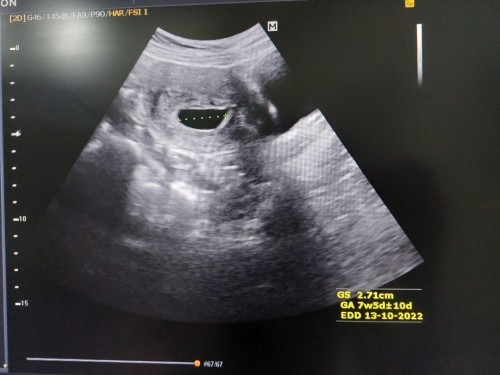

นับตามประจำเดือนหมดครั้งสุดท้าย ได้อายุครรภ์ 10 w 1d วันนี้ไปซาวด์หมอบอกตอนนี้อายุครรภ์ 7w 5d แต่ยังไม่เห็นตัวเด็กเลย แต่บ้านนี้มีความเสี่ยงแท้งคุกครามด้วย พอจะมีหวังจะเจอน้องไหม #ขอคำแนะนำหน่อยค่ะ #คุณแม่ๆช่วยแนะนำหน่อยค่ะ #ขอบคุณสำหรับคำตอบค่ะ